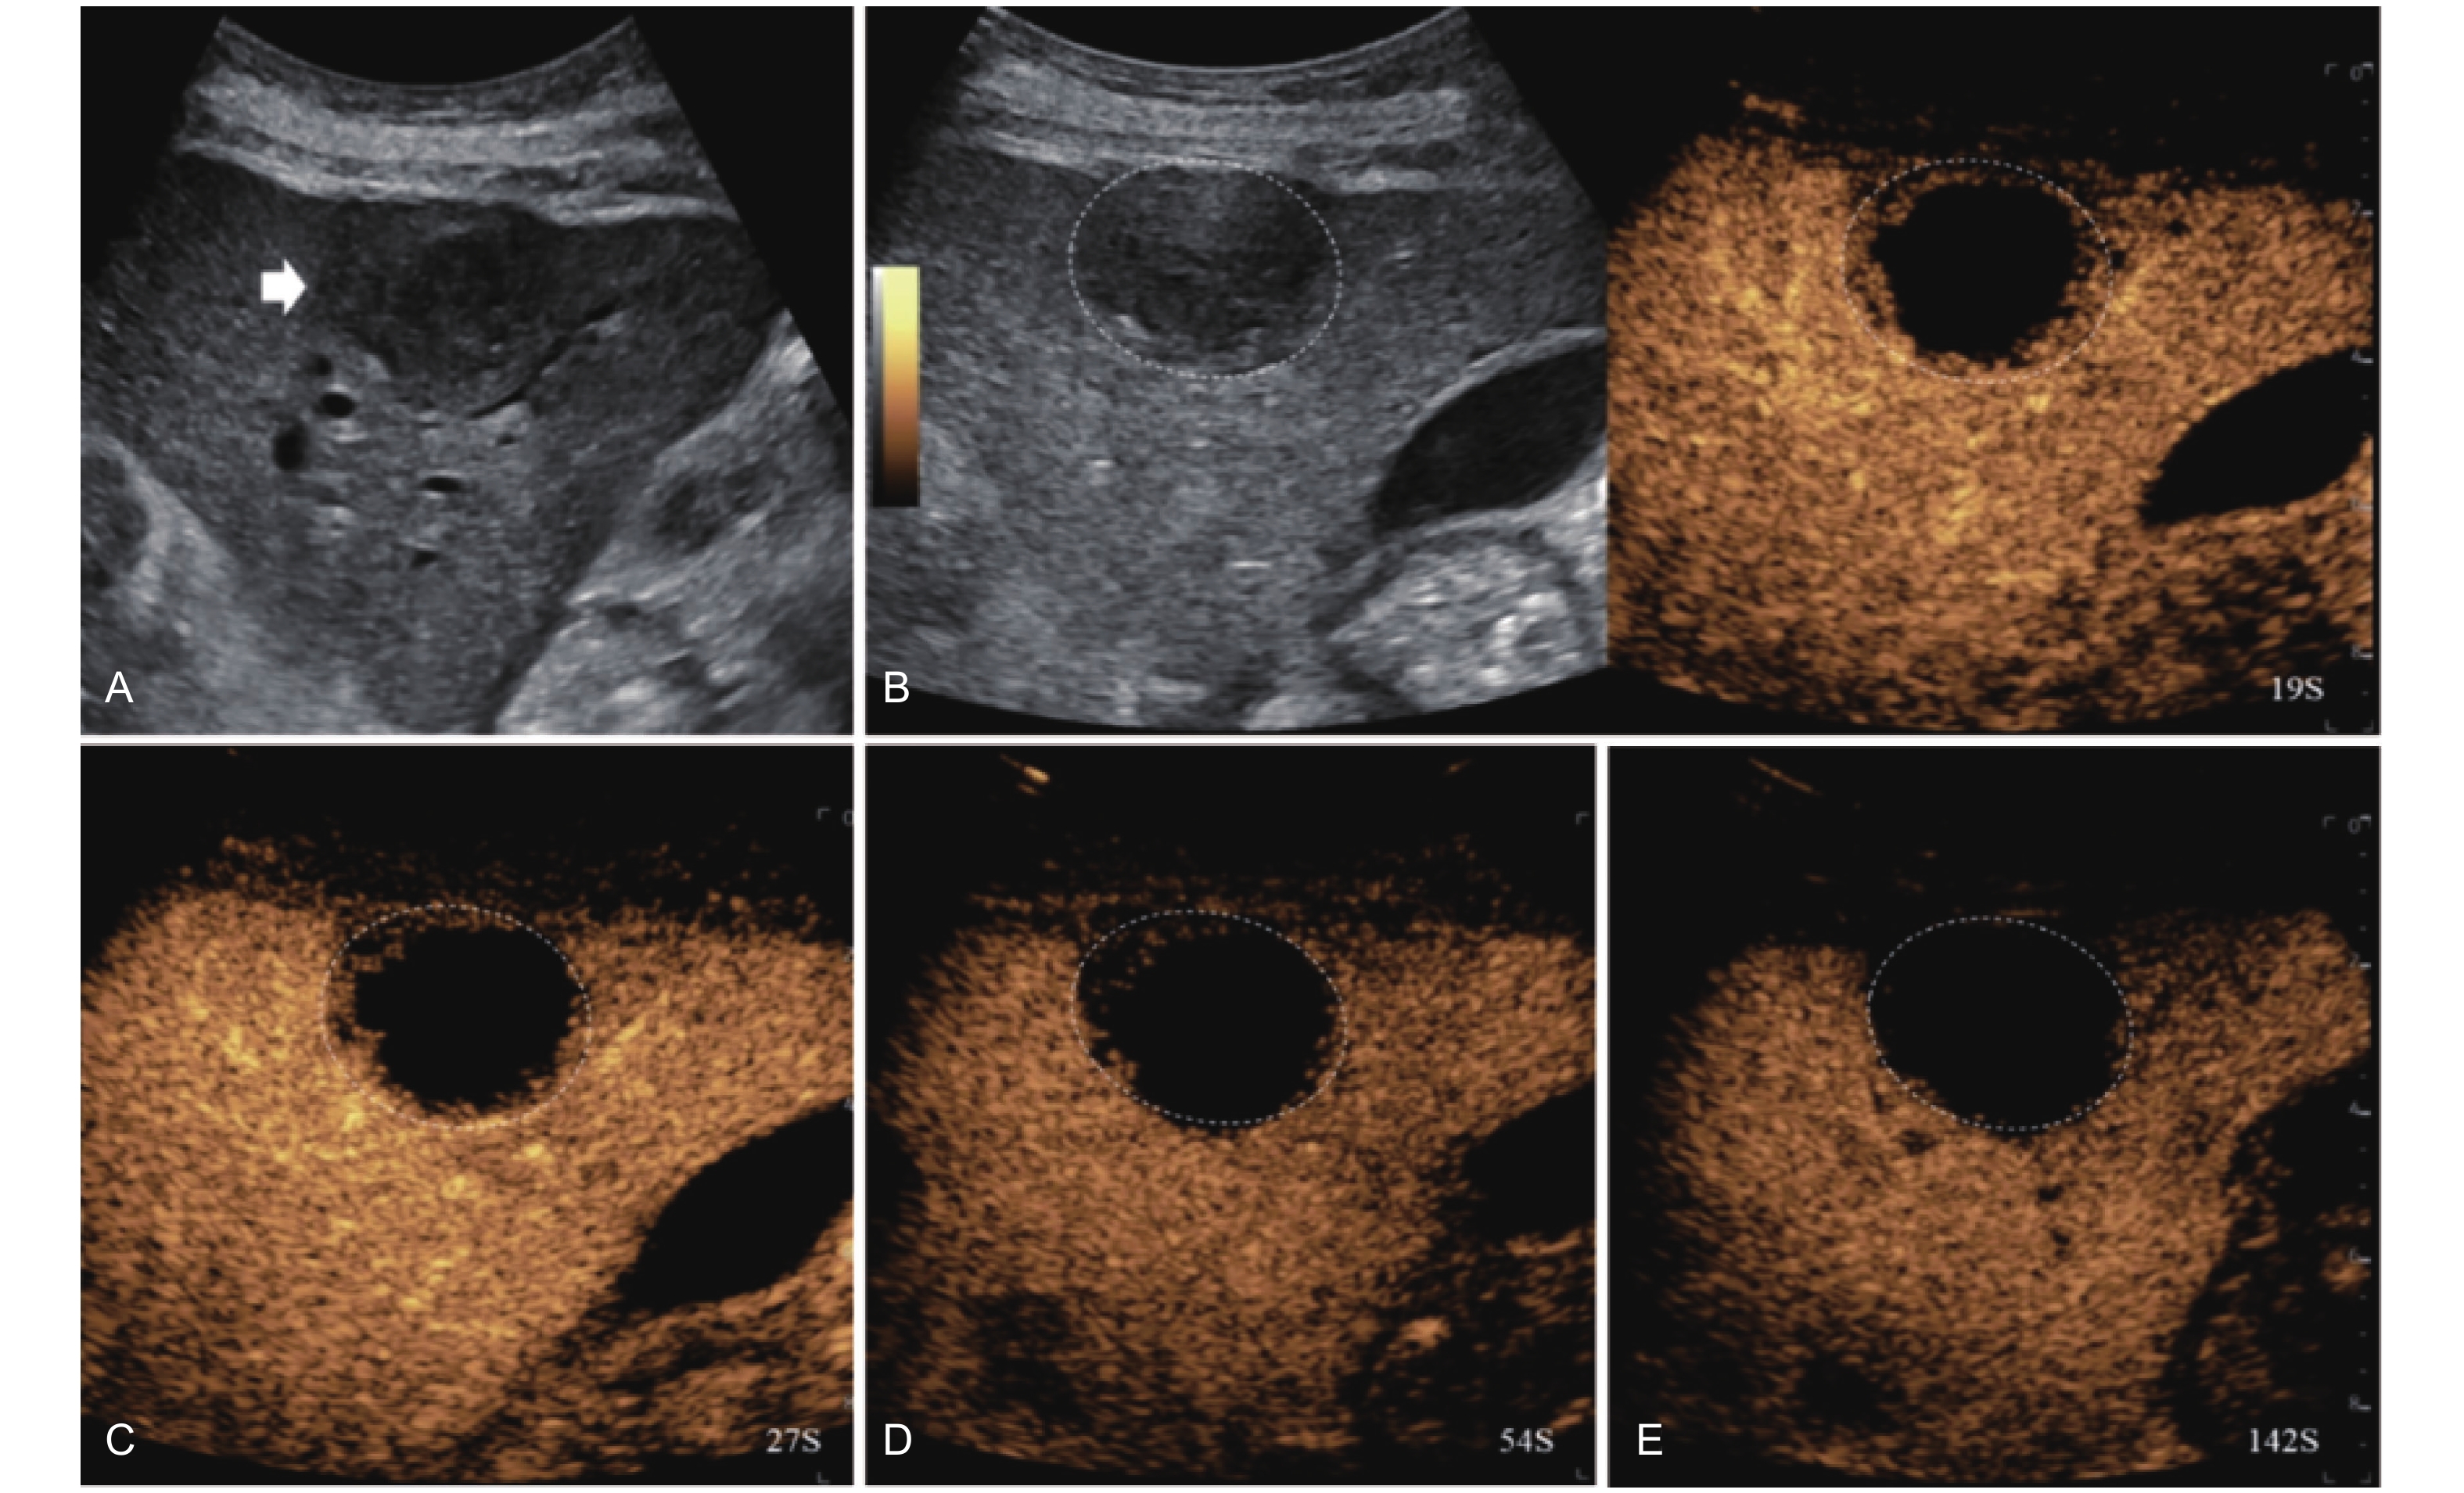

Figure 10

LR-TR Viable. A 56-year-old male with HCC, 1 year after RF ablation. (A) B-mode image shows a heterogeneous mildly hypoechoic lesion (thick arrow) with poor-defined margins in segment VII; (B) Post-treatment CEUS shows intralesional heterogeneous hyperenhancement; (C) The lesion shows mild washout in the portal venous phase; (D) The lesion shows marked washout in the late phase. Perilesional enhancement remains identical to the surrounding liver parenchyma throughout all phases. Findings are consistent with LR-TR Viable. (This case and figures were contributed by Dr. Qiang Lu from Huaxi Hospital of Sichuan University)"